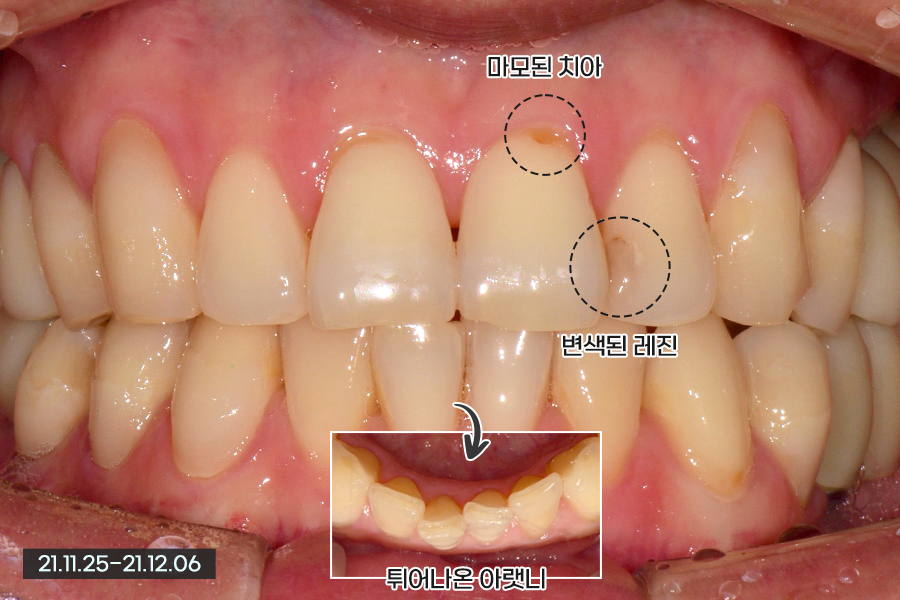

30대 초반의 남성 환자분이신데, 전반적으로 치아가 가지런한 상태이지만 앞니에 마모된 부분이 있고 레진이 변색된 부분도 있었습니다. 그리고 뒷 부분의 치아는 대부분 다 임플란트 치료를 받은 상태였습니다.

앞에서는 잘 안보이지만 아래 치아가 튀어나와 있어 앞니의 끝과 끝이 닿는 상태였습니다. 때문에 이 부분은 조금 삭제가 이루어져야 하는 상황이었습니다.